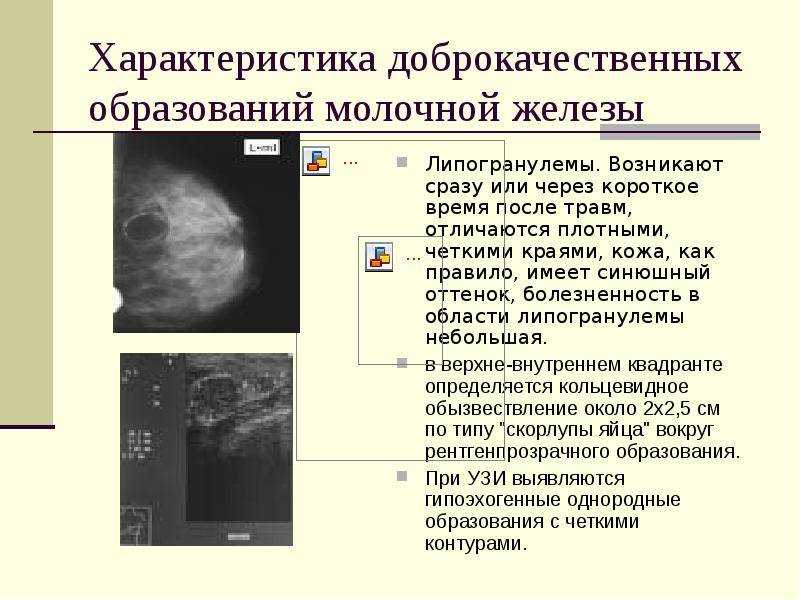

Злокачественная фиброаденома молочной железы. Фиброаденома молочной железы Размеры для операции. Фиброаденома молочной железы маммография. Листовидная опухоль гистология. Доброкачественная опухоль. Доброкачественныеопкхоли. Клетки, образующие доброкачественную опухоль:. Строение доброкачественной опухоли.

Доброкачественная опухоль. Доброкачественныеопкхоли. Клетки, образующие доброкачественную опухоль:. Строение доброкачественной опухоли. Гиповаскулярные метастазы печени кт. Опухоль желудка метастазирование.

Петрокливальная менингиома. Менингиома доброкачественная. Злокачественные заболевания молочных желез. Новообразование молочной железы. Злокачественная опухоль молочной железы. Доброкачественные новообразования молочной железы.

Глиобластома мультиформная степень 4. Неоперабельная глиобластома головного мозга.. Глиобластома лобной доли мрт. Глиобластома злокачественная опухоль агрессивная. Филлоидная фиброаденома молочной железы УЗИ. УЗИ признаки доброкачественных опухолей молочных желез. Доброкачественная опухоль молочной железы на УЗИ. Опухоль молочной железы на УЗИ.

Филлоидная фиброаденома молочной железы УЗИ. УЗИ признаки доброкачественных опухолей молочных желез. Доброкачественная опухоль молочной железы на УЗИ. Опухоль молочной железы на УЗИ. Хирургическая операция. Эндоскопическая операция. Хирургическое вмешательство. Эндоскоп хирургический.